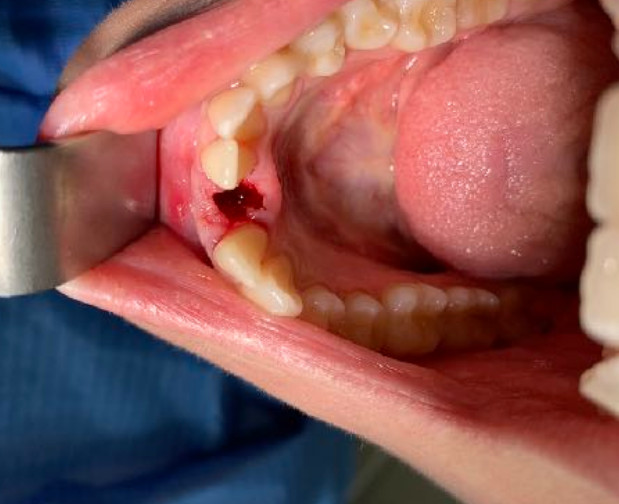

| Situazione estrattiva: Impianto postestrattivo immediato a carico immediato. | Densità secondo Misch: D2 |

Il diametro ridotto del collo consente di mettersi al riparo da eventuali periimplantiti e migliora nettamente la velocità della guarigione. In questo caso è stato maschiato con un diametro 4 ed è stato inserito un impianto di Tramonte diametro 4 mm a 7 spire a collo corto . Il titanio utilizzato è sempre di grado 4.

| Sequenza frese: Solo fresa lanceolata | Sequenza maschiatori: maschiatore diametro 4 mm |